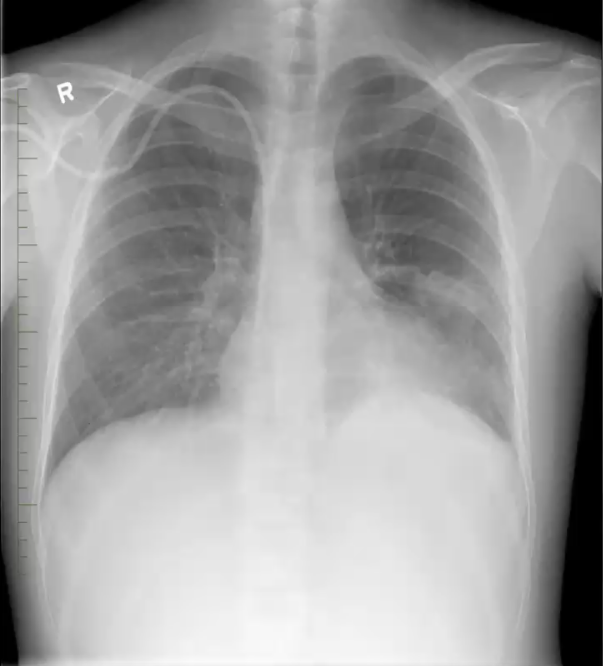

What’s your diagnosis?

Right middle lobe pneumonia because loss of right heart border (silouhette sign)